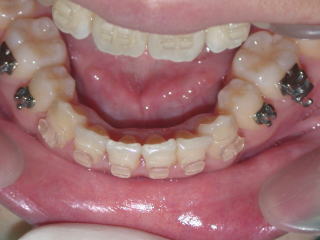

術前術後

2022年7月→2024年5月(2年弱でした。これから保定期間に入ります。)